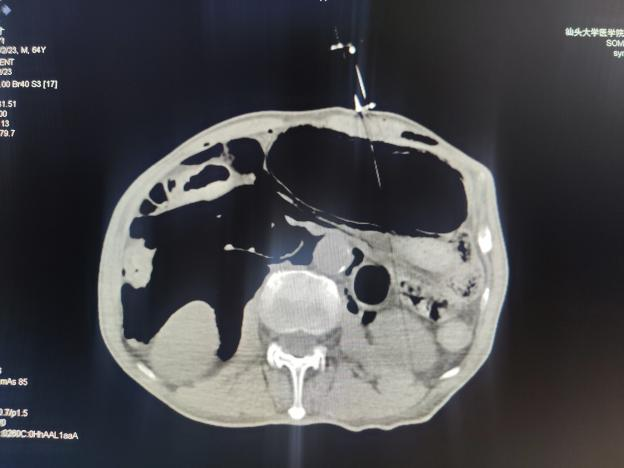

关键时刻,肿瘤医院微创介入科易长虹副主任经评估后决定为患者行CT引导下经皮胃造瘘术。术程顺利,术中创伤小,术后24小时即可喂食,成功为患者解决饮食营养问题,提高生活质量。

CT引导下经皮胃造瘘术

CT引导下经皮胃造瘘术是一种特殊的管饲营养方法,主要用于经口摄食困难而又有正常胃肠功能的病人。这项技术主要是在CT引导下,经腹部皮肤穿刺放置胃造瘘管,营养物质通过造瘘管直接注入胃内,为需长期管饲营养支持的病人提供另一种进食方法。